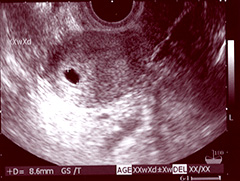

妊娠5週1日頃、GS8.6mm…1cmにも満たないちっちゃな胎嚢。

朝からかかりつけの産婦人科を受診。お小水を提出したあと、内診室へ移動。最初に分泌物の状態を確認したあと触診、痛みがないか聞かれる。次は、いよいよエコー検査。下半身で仕切られていたカーテンをシャッと開けて、先生がモニターを見せてくれた。

……あった。白い画像の中に、黒い胎嚢がポツンと!! 直径は8.6mm。まだ1cmにも満たないけれど、くっきり袋が写ってる。少し角度をずらすと、卵黄嚢もうっすら見えた。

心拍はまだ見えないので、来週、再度受診することに。最後に「おめでとうございます」と先生。まだ心拍も見えない段階だから、「おめでとう」は早過ぎるかなと思っていたけれど、言われるとしみじみ嬉しくなってきた。